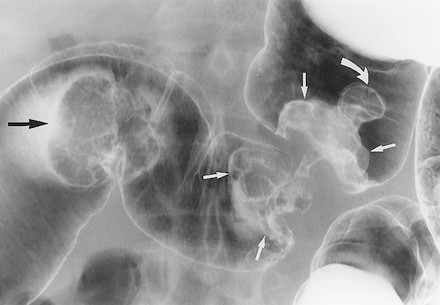

Ung thư biểu mô hình khuyên hay phát triển ở vùng sigma nhất nhưng cũng có thể thấy ở đại tràng xuống, đại tràng ngang, và đại tràng lên. Trái lại, chúng không xảy ra ở manh tràng và trực tràng do khẩu kính của các đoạn đó lớn. Các tổn thương hình khuyên biểu hiện trên phim cản quang baryt bằng hẹp chu vi lòng ruột, với sự phá hủy niêm mạc, với các bờ nhô lên như dải đá ngầm (Hình 11, 12). Chủ yếu phải quan sát các quai ruột tách nhau, nếu quai ruột chồng nhau có thể không quan sát thấy tổn thương (Hình 12).

Hình 11. Hình cản quang kép khu trú, bệnh nhân nằm ngửa phát hiện hai ung thư biểu mô tuyến đồng thời. Khối ung thư biểu mô hình khuyên ở đoạn cuối đại tràng ngang đặc trưng bởi sự phá hủy niêm mạc và các bờ nhô lên hình đá ngầm (mũi tên trắng, thẳng). Khối ung thư biểu mô tuyến thứ hai dạng polyp (mũi tên đen) nằm ở đoạn đầu đại tràng ngang. Bệnh nhân này cũng có một polyp tuyến (mũi tên trắng, cong) ở sát bờ ngoài tổn thương hình khuyên.

Ung thư biểu mô hình polyp thường thấy ở manh tràng hoặc trực tràng; có giả thuyết cho rằng do khẩu kính của các đoạn ấy to. Giống như các polyp đại tràng, các ung thư biểu mô hình polyp ở thành không đọng thuốc xuất hiện dưới dạng khuyết trong vũng baryt, trong khi các tổn thương ở thành không đọng thuốc là đường khắc màu trắng (Hình 13a, 13b). Để bộc lộ các khối u hình polyp khi chụp cản quang kép yêu cầu phải làm giãn quai ruột đầy đủ, đặt tư thế bệnh nhân đúng, và ép vũng baryt bằng tay một cách cẩn thận. Các khối hình polyp có thể bị bỏ sót nếu quai ruột không được làm căng đầy đủ (Hình 14).